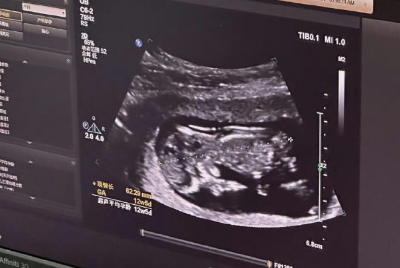

女性检查项目:包括妇科常规检查、B超(评估卵巢和子宫状况)、内分泌激素水平检测、AMH(卵巢储备功能评估)、染色体核型分析、传染病筛查(乙肝、丙肝、梅毒、艾滋病等)、TCT和HPV筛查、心电图、凝血功能等。

卵泡监测:在促排卵期间,医生会通过B超和抽血(监测激素水平)来实时跟踪卵泡的生长发育情况,以便及时调整用药。

当卵泡发育成熟后,医生会在B超引导下进行取卵手术。同时,男性会进行取精。随后,卵子和精子将在实验室中进行体外受精和胚胎培养。